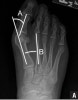

체중부하 상태의 AP view에서 계측합니다.

제1중족골과 무지근위지골의 장축이 이루는 각도가 외반무지각(HV angle)으로 통상 8º 이내, 1530º를 경도, 3040º를 중등도, 그 이상은 중증도입니다.

IM angle이 통상 8º 이내, 13º까지를 경도, 20º까지를 중등도, 그 이상은 중증도입니다.

DMA angle의 정상 범위는 10º이내입니다.

X-ray : 무지외반증(Hallux valgus)